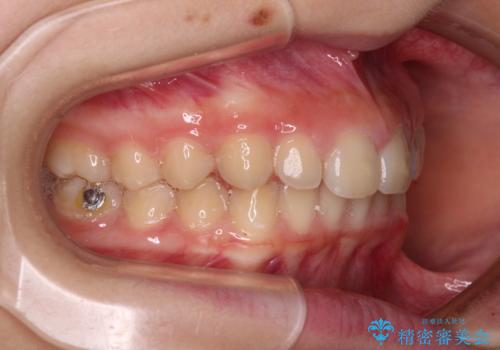

- ヨーロッパにてインビザライン矯正を始めたものの、日本に転居することになり、治療の継続を希望して来院された患者様です。

治療計画に無理がなく、現地担当医と速やかに連絡が取れるとのことで、インビザライン社での転医手続きを行い、継続して治療を行うこととしました。

舌の突出癖により、上下前歯が非接触となっていたため、トレーニングを徹底的に指導し、安定した咬み合わせにより終了させることができました。